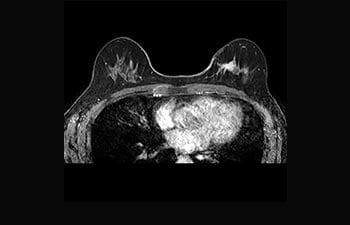

Enhanced diagnostic confidence in neuro oncology